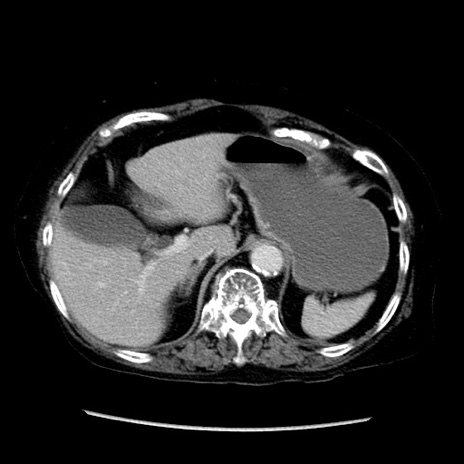

症例14(横断像)

【症例】 90歳代女性

【主訴】 腹痛・嘔吐

【現病歴】今朝から左側腹部痛を認めた。 経過観察していたが、嘔吐を認めたため来院。

【既往歴】 子宮癌術後

【身体所見】 意識清明、BP 127/54mmHg、P 98bpm Sp02 95%(RA)、BT 35.8°C、腹部平坦・軟腸ぜん動音聴取良好、右下腹部圧痛(+) 反跳痛なし

【データ】WBC 9800、CRP 0.46